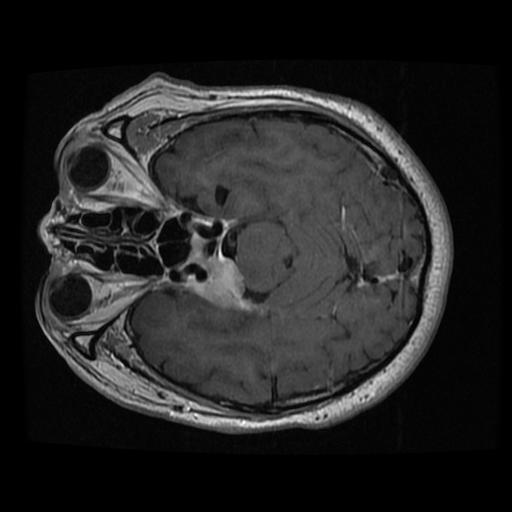

Screenshots